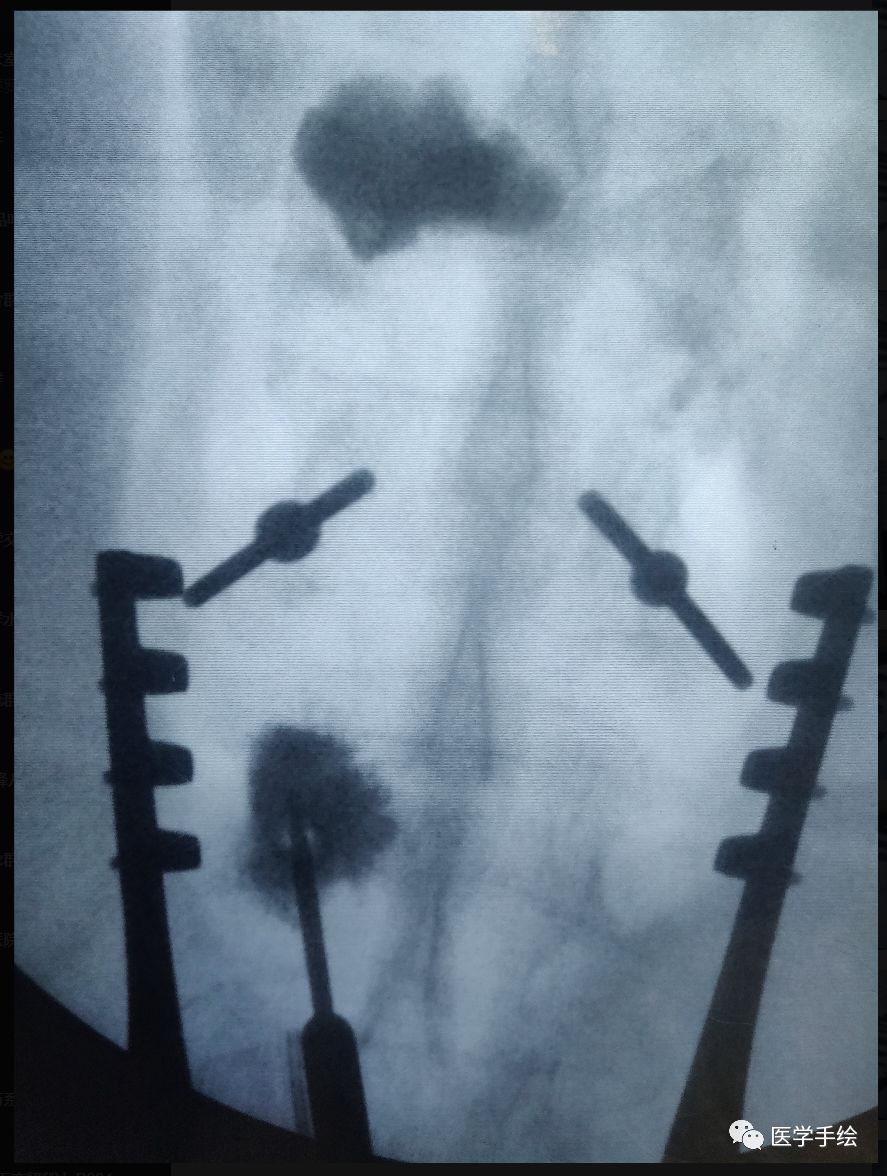

case:老年骨质疏松患者,既往L2行单侧(左侧)椎体成形手术。本次手术L2需要置入螺钉,左侧椎弓根螺钉由于骨水泥的存在置入困难,选择CBT螺钉。